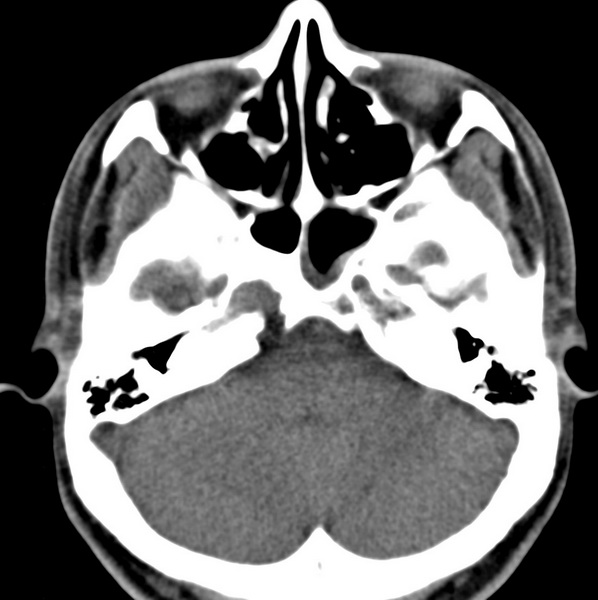

男、31、鼻咽部肿瘤放疗后请帮忙看看。

效果好,右侧破裂孔扩大,局部骨质缺损,为颅底骨质破坏。

1)鼻咽部肿瘤侵犯颅底放疗术后改变。2)左侧蝶窦炎。

咽后壁增厚,左侧咽鼓管隆突增大、咽鼓管咽口变浅,同侧咽旁间隙较窄。右侧颅底骨质破坏?为什么不在同一侧?

鼻咽部肿瘤侵犯颅底放疗术后改变.